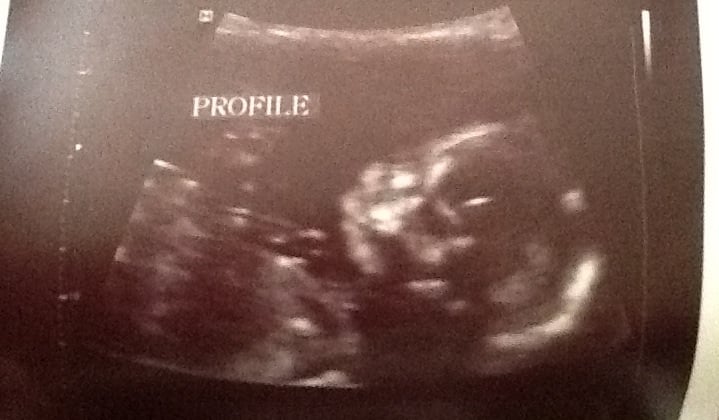

Today I had my anatomy scan and we are officially team BLUE!!! We finally told everyone today 18.1w after knowing the guess at the NT scan at 12 weeks, it was hard keeping it from everyone, but glad we waited until it was official. We are so happy everything went well and happy our first is a boy. I started feeling the baby move last week and it has gotten stronger and more frequent. Now I've started to feel him while standing too. What a great feeling. I can't wait until DH can feel it from the outside. H&H 9 months to all fellow bumps.